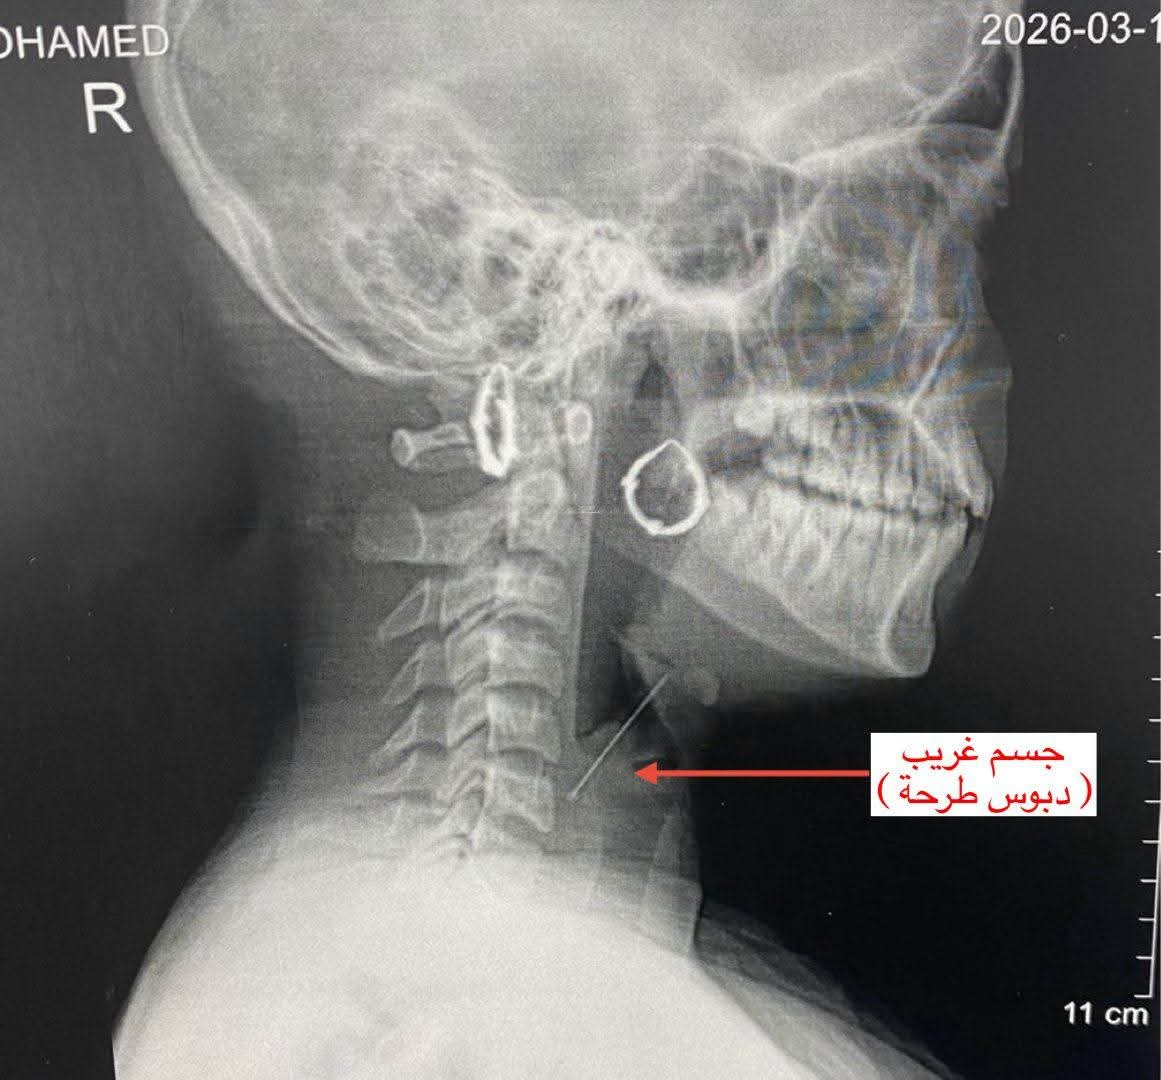

استقبل قسم الطوارئ بالمستشفى الفتاة وهي تعاني من آلام شديدة في الرقبة وصعوبة في التنفس. أجريت الفحوصات اللازمة والأشعة التي أكدت وجود الجسم الغريب في منطقة دقيقة بالمجرى التنفسي مما كان يشكل خطرًا على حياتها.